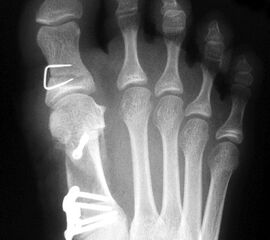

Im eigenen Patientengut wurden bei entsprechender Indikation 35 konsekutive Füße mit Hallux valgus und einem Intermetatarsalwinkel von >14° (range 14 – 23°) mit einer proximalen Open wedge-Osteotomie des Metatarsale I behandelt. Die verwendete winkelstabile Platte (Pedus-O, Axomed GmbH) zeichnet sich durch einen Steg aus, welcher sich im Osteotomiespalt verklemmt und gleichzeitig die Stellung sichert.

Das durchschnittliche Alter lag bei 43,7 Jahre (Range: 19-72 Jahre), es wurden 27 Frauen und 8 Männer behandelt. Bei 15 Patienten die Basisosteotomie mit einer Akin-Osteotomie der Grundphalanx kombiniert. Patienten mit Doppelosteotomien am Metatarsale I wurden von der Untersuchung ausgeschlossen.

Entsprechend der präoperativen Planung wurde ein Steg von 2 bis 6 mm Breite gewählt, wobei bei 15 Patienten die Stegbreite von 4 mm eingesetzt wurde. Die Stegbreite von 3 mm kam in 10 Fällen und die Stegbreite von 5 mm in 5 Fällen zur Anwendung. Der Osteotomiespalt wurde locker mit Spongiosa aus der resezierten Pseudoexostose aufgefüllt. Analysiert wurden der postoperative Verlauf und die erzielte Korrektur sowie das klinische und radiologische Ergebnis nach 6 Monaten.

In zwei Fällen kam es intraoperativ zu einem Bruch der lateralen Kortikalis. In einem Fall konnte durch die winkelstabile Platte eine ausreichende Stabilität erzielt werden, in dem anderen Fall wurde zusätzlich ein perkutaner Kirschnerdraht eingebracht, der nach 6 Wochen entfernt wurde. Eine stabile knöcherne Konsolidierung der Osteotomie ohne Korrekturverlust konnte in beiden Fällen erreicht werden. Die Analyse der Röntgenaufnahmen ergab eine Verlängerung des Os metatarsale I von durchschnittlich 1,8 mm (Range 1-4 mm).